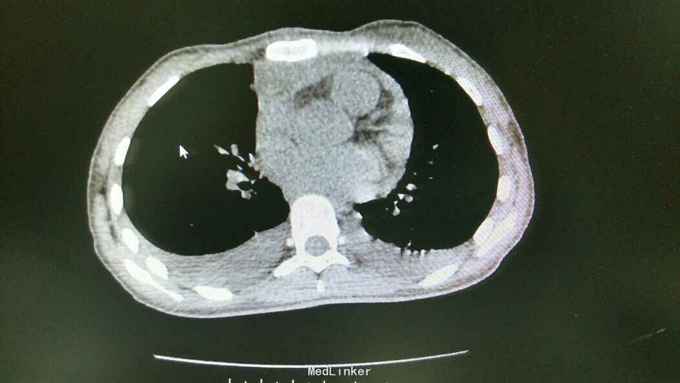

查体:T37.0℃,P110次/分,R26次/分,BP96/68mmHg。发育正常,营养一般,神志清楚,对答切题,轮椅送入院,查体合作。全身皮肤粘膜无黄染、皮疹,出血点及淤斑,未见Janeway结节,未见Osler结节及甲床下出血,无发绀,未见杵状指、趾,周围血管征阴性。浅表淋巴结未及肿大。巩膜无黄染,结膜无出血。口腔黏膜光滑,咽不红,扁桃体部大,颈静脉无明显搏动,未见怒张,气管居中,胸背部听诊双下肺闻及细小湿啰音。心前区无隆起或抬举性搏动,心尖搏动以左侧第六肋间锁骨中线外1.5cm处明显,未扪及震颤,心界向两侧稍扩大,心率110次/分,律齐,心音有力,P2稍亢进,无固定分裂,心尖区闻及3-4/6级收缩期吹风样杂音,向心底部传导,未闻及舒张期杂音,未闻及心包摩擦音。腹平软,无压痛及反跳痛,肝脾肋下未及,肠鸣音正常。脊柱、四肢关节无异常,活动好,双下肢无浮肿。 2015年10月30日汕头市中心医院心彩超:二尖瓣及瓣下腱索及左室心内膜多发赘生物形成,二尖瓣前瓣穿孔,重度二尖瓣关闭不全,左心系统扩大,心肌舒张功能下降,收缩功能正常,感染性细菌性心内膜炎,微量心包积液。 2015-11-1血常规:中性粒细胞比例 0.949,血红蛋白浓度 117.000(g/L),中性粒细胞计数 18.360(10E9/L),白细胞计数 19.350(10E9/L),血小板计数 343.000(10E9/L),红细胞计数 4.350(10E12/L)。 B超:双侧颈动脉血流通畅,双侧椎动脉未见狭窄。双侧甲状腺不大、未见占位,血供尚丰富。双侧颈部淋巴结声像,双侧乳腺未见明显占位,超声BI-RADS分类1类,双侧腋窝淋巴结声像。双肾未见结石与积水,双肾动脉主干血流连续,膀胱未见明显结石,双侧肾上腺区未见明显占位。肝脾胰不大,未见占位,胆囊未见明显结石,子宫及双侧附件区未见明显占位,宫后积液(少量)。 胸部CT:1、两下肺叶后基底段局部节段性肺炎。右肺中叶少许纤维化病灶。2、双侧胸腔少量积液。 胸片:考虑双肺炎症。 心电图:心率84次/分,窦性心律,肢体导联低电压,前间壁R波上升不良。 心彩超:1、考虑感染性心内膜炎:二尖瓣赘生物形成,伴中重度二尖瓣反流。中度三尖瓣反流。3、左房内径增大,肺动脉增宽。 头颅MR:左侧额叶、左侧放射冠侧脑室前角旁脑白质异常信号,考虑感染性病变及缺血灶可能性大。 2015-11-2查血常规:中性粒细胞比例 0.840,血红蛋白浓度 103.000(g/L),中性粒细胞计数 14.730(10E9/L),白细胞计数 17.540(10E9/L),红细胞计数 3.890(10E12/L),血小板计数 353.000(10E9/L)。 10月31日左上肢、右上肢、下肢血培养均提示:草绿色链球菌,对万古霉素敏感。 2015-11-6肾功能:肌酐 130.000(umol/L),尿素氮 5.250(mmol/L),二氧化碳结合力 30.500(mmol/L),电解质:钠 138.000(mmol/L),氯 96.000(mmol/L),钾 3.500(mmol/L),钙 2.310(mmol/L),肝功能:白、球蛋白比例 1.300,未结合胆红素 10.500(umol/L),总胆红素 17.900(umol/L),丙氨酸氨基转移酶 31.000(U/L),总蛋白 75.000(g/L),球蛋白 32.000(g/L),白蛋白 43.000(g/L),结合胆红素 7.400(umol/L),门冬氨酸氨基转移酶 31.000(U/L),脑钠肽:191.400(pg/ml)。 24小时心电图:窦性心律,房性早搏,部分成对,短阵房速,多源室早,部分成对,部分呈三联律,短阵室速。